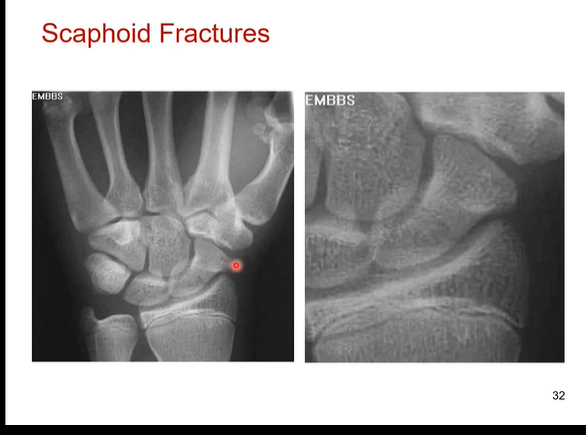

Does the scaphoid bone have poor blood supply? What does this mean for healing if you have a scaphoid fracture

Yes scaphoid bone has poor blood supply. it takes a long time to heal cause it gets only a little bit of oxygen